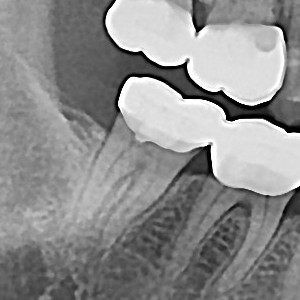

충치치료&신경치료 하루에 끝나는 신경치료